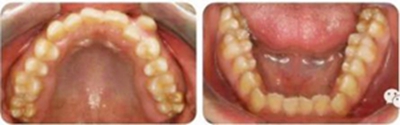

張某,男性,13歲,主訴前牙反頜伴開頜,要求矯治。

正面觀雙側(cè)基本對(duì)稱,垂直向基本協(xié)調(diào);側(cè)面觀直面型,下頜平面角較陡。顳下頜關(guān)節(jié)未見(jiàn)異常。

恒牙列,上中線右偏2mm,下中線左偏3mm,左側(cè)尖磨牙Ⅰ類 ,右側(cè)尖磨牙Ⅲ類。前牙反頜,13唇側(cè)低位萌出。上牙列擁擠度10mm,下牙列擁擠4mm。

(1)安氏Ⅲ類亞類錯(cuò)合;

(2)前牙開頜、反頜;

(3)13唇側(cè)低位萌出。